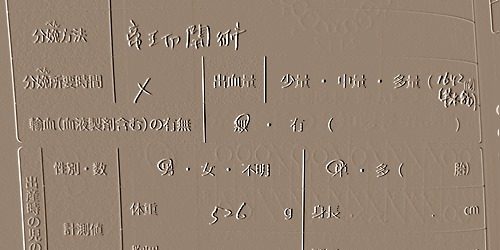

妊娠24w1d、緊急帝王切開にて526gでミニ太を出産したハハ。 母子手帳に付属していた妊婦検診の補助券を半分も使い切らずに出産す…

ハハの重症妊娠高血圧腎症により24週1日でこの世に誕生したミニ太。526g。 人生最初(で最後の)帝王切開手術について、思い出せる…